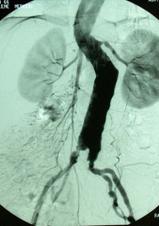

Anevrizma tanısında özellikle tedaviyi planlamak için başka yöntemlerde kullanılmaktadır. Bunlar bilgisayarlı tomografi, manyetik rezonans görüntüleme ve anjiografidir.

Bu yöntemler ile anevrizmanın ne kadar büyük olduğu (tedavi planlamasının en önemli öğesidir), nerede olduğu ve hangi organlarla ilişkide olduğu belirlenir. Anjiografi cerrahi girişimi plnalamak için genelde gerekmez, ama endovasküler anevrizma onarımı planlanırken çektirilmesi uygundur.

Daha az rahatsızlık verebilecek bir başka tedavi yöntemi ise özel bazı kateterler ile damarın içine girilip, anevrizmanın olduğu damar bölümüne içerden suni damarın yerleştirilmesidir. Endovasküler (damar içinden) anevrizma onarımı olarak bilinen bu yöntem yaklaşık 10 yıllık bir geçmişe sahiptir. Bu yöntemde karından kesi yapılmayıp, sadece kasıklardan yapılan küçük kesiler aracılığı ile röntgen altında işlem gerçekleştirilir.

Anevrizmanın olduğu yere getirilen suni damar şişirilir ev dikiş yerine içerden özel kancalar ile damar tutturulur. Hastalar işlem sonrası hastanede bir iki gün yatıp taburcu edilirler. Bu yöntem anevrizmalı hastaların ancak bir bölümü için uygundur. Anevrizmanın içine suni damar yerleştirildikten sonra anevrizma büyümeye devam edebilir hatta rüptüre olabilir. Bu yüzden hastaların işlem sonrası aralıklı olarak bilgisayarlı tomografi veya renkli Doppler ultrasonografi ile takibi gereklidir. Bu açıdan bu yöntem açık ameliyat yönteminin tersine anevrizmayı her zaman kalıcı olarak tedavi etmez.